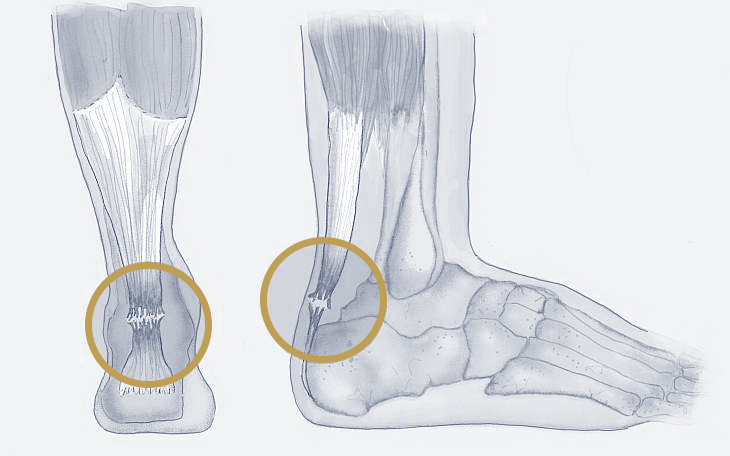

Bildquelle: www.docset.de

Symptome

Typisch ist ein plötzlicher, stechender Schmerz im Bereich der Achillessehne, oft begleitet von einem Knallgeräusch. Viele Betroffene beschreiben das Gefühl, einen Tritt gegen die Wade bekommen zu haben. Das Gehen ist oft nur noch eingeschränkt möglich, und der Zehenstand ist nicht mehr durchführbar.

Ursachen

Häufige Ursachen sind eine plötzliche, explosive Belastung der Sehne, z. B. beim Sport, eine Vorschädigung der Sehne durch eine Achillodynie oder vorausgegangene Infiltrationen mit Kortison.

Konservative Therapie

Die konservative Therapie besteht in der Ruhigstellung des Fußes in Spitzfußstellung für mehrere Wochen, gefolgt von einer langsamen Steigerung der Belastung. Diese Methode ist jedoch mit einem höheren Risiko für eine erneute Ruptur verbunden.

Operative Therapie

Die operative Therapie besteht in der Naht der gerissenen Sehne. Diese Methode ermöglicht eine schnellere Rehabilitation und ein geringeres Risiko für eine erneute Ruptur.